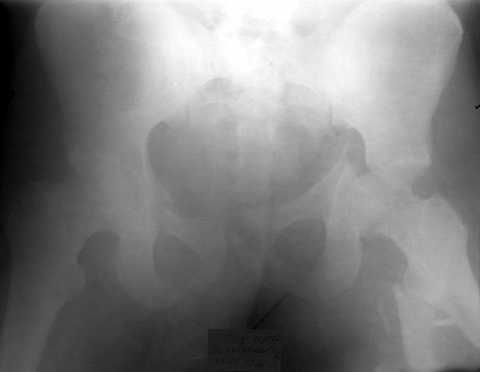

Уважаемые коллеги. Пациент 22 лет поступил 10.08.03. после ДТП. 11.08. жировая эмболия с суточной комой. В настоящее время в сознании, имеются невыраженные психические нарушения. Проводится скелетное вытяжение грузом 13кг.

В плане одномоментное вправление вывиха, наложение АВФ на бедро и скелетное вытяжение по оси и боковое за центральный отломок по оси шейки. Возможны ли варианты лечения в условиях ЦРБ?